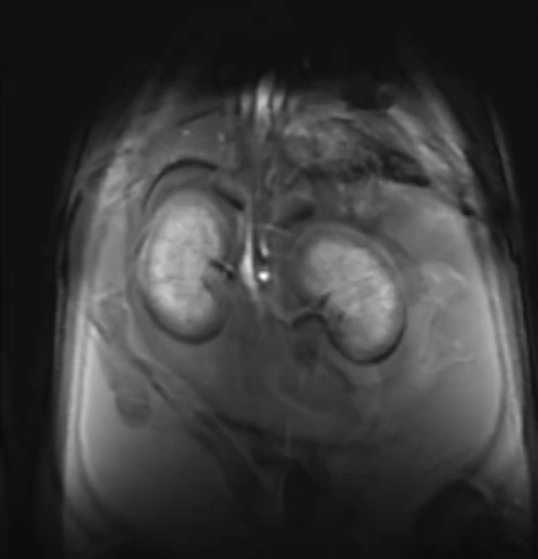

Le Centre abrite le seul appareil d’IRM pour petits animaux à grand champ de la région d’Ottawa (système Discovery MR901 de 7,0 Tesla d’Agilent Technologies / General Electric). Il n’y a qu’environ 10 machines de ce type dans tout le Canada qui offrent une occasion unique de tirer parti de cette ressource et d’obtenir un avantage dans le contenu de votre manuscrit.

Le système d’IRM est équipé d’un aimant supraconducteur à alésage horizontal de 7,0 T et 310 mm de diamètre, interfacé avec la plateforme Signa HDx de General Electric. Le système offre des capacités de recherche préclinique en IRM de haute qualité et robustes avec une variété de contrastes d’imagerie et d’évaluations quantitatives. CIPC fournit un service pour répondre à un large éventail de besoins des chercheurs, de l’imagerie d’animaux vivants aux recherches d’échantillons, la caractérisation d’agents de contraste à la recherche de matériaux et de plantes.

L’imagerie est réalisée à l’aide d’un puissant système de gradient de 300 mT/m (30 Gauss/cm) (diamètre intérieur de 210 mm) équipé d’une capacité de cale d’ordre 2. Une large gamme d’antennes de radiofréquence (bobines) sont disponibles, allant des antennes de corp aux antennes de réception dédiées et activement découplées pour le cerveau de souris et de rats. Des systèmes de surveillance physiologique et de manipulation des animaux sont également disponibles. Le spectromètre IRM est équipé de capacités X-nuclei.

Exemples d'images acquises par notre IRM 7T